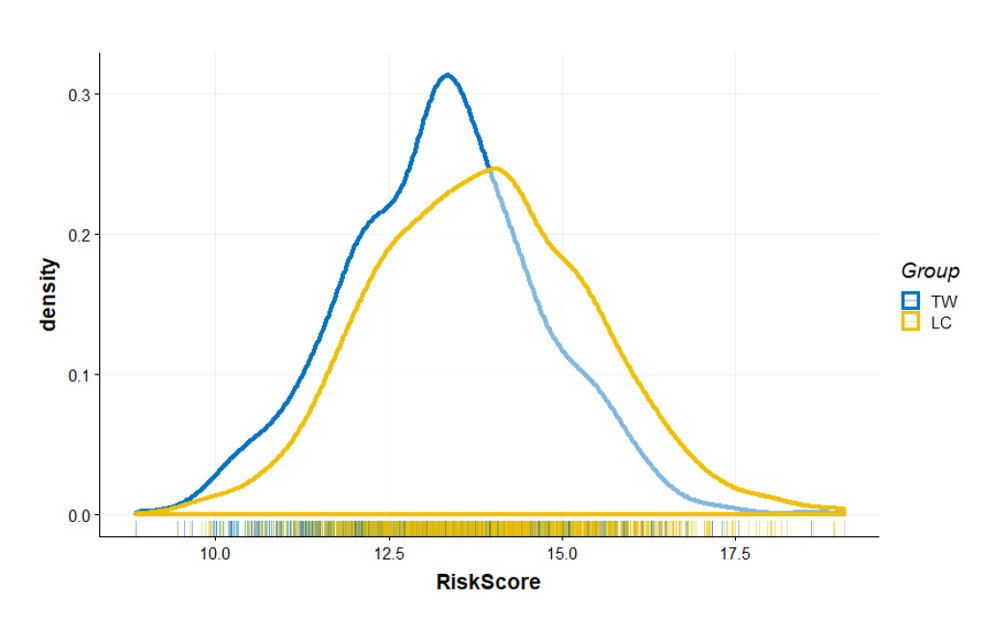

- Thông qua cơ sở dữ liệu công khai và tiên tiến, chúng tôi đã tổng hợp tất cả các vị trí đa hình nucleotide đơn (SNP) liên quan đến ung thư phổi và tạo ra một mô hình dự đoán rủi ro duy nhất. Chúng tôi không chỉ sử dụng thông tin bộ gen của những người khỏe mạnh trong cơ sở dữ liệu như Dự án 1000 gen và Ngân hàng sinh học Đài Loan, mà còn kết hợp nó với dữ liệu bộ gen quý giá của bệnh nhân ung thư phổi để đảm bảo rằng mô hình của chúng tôi có thể phản ánh một cách chính xác mức phân phối rủi ro ung thư phổi trong dân số.

- Vì vậy chúng tôi đã tiến hành cuộc khảo sát chi tiết cho mỗi người tham gia, từ lịch sử bệnh gia đình, hồ sơ sức khỏe trước đây đến lối sống và môi trường sống. Mọi thông tin này đều quan trọng trong quá trình đánh giá của Googene. Khi tất cả dữ liệu được tổng hợp lại, mô-đun phân tích rủi ro ung thư phổi của chúng tôi sẽ thực hiện phân tích chính xác để đảm bảo bạn có được đánh giá rủi ro chi tiết nhất.

- Sau khi phân tích chuyên môn chúng tôi chia nguy cơ ung thư phổi thành ba mức độ: thấp, trung bình và cao. Được xếp vào nhóm rủi ro cao không đồng nghĩa với việc bạn chắc chắn sẽ mắc ung thư phổi trong tương lai, nhưng nó thể hiện rằng khả năng mắc bệnh so với đại đa số sẽ cao hơn.